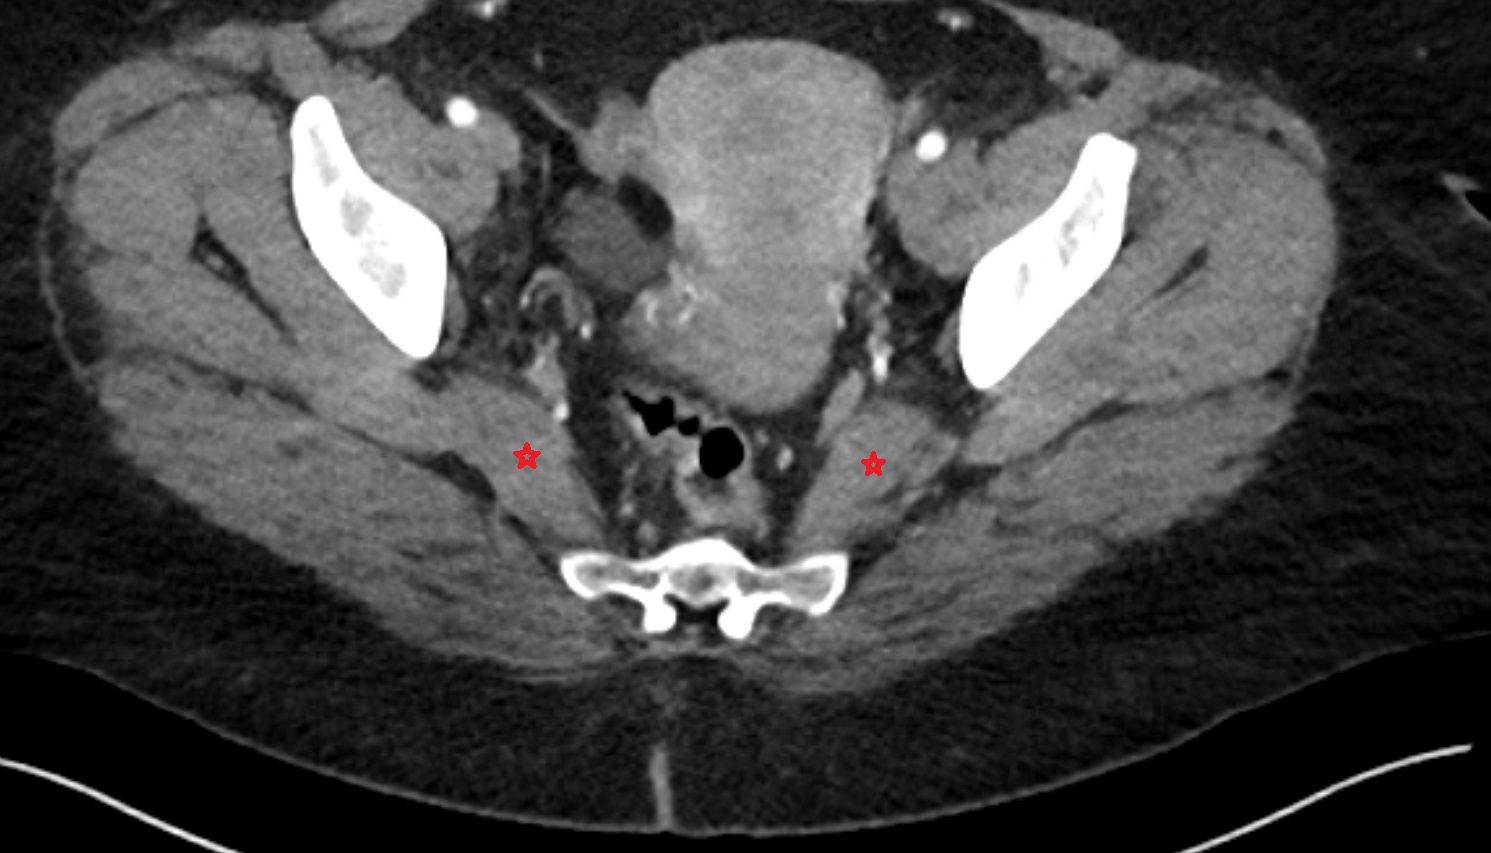

- Piriformis muscle

- Obturator internus muscle